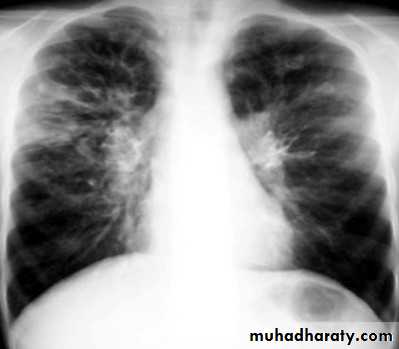

Bronchiactasis

Bronchiectasis refers to abnormal dilatation of the bronchial tree and is seen in a variety of clinical settings. CT is the most accurate modality for diagnosis. It is largely considered irreversibleCauses of bronchiactasias very important to consider

Plain radiograph

Chest x-rays are usually abnormal

1. Tram-track opacities are seen in cylindrical bronchiectasis, and

2. air-fluid levels may be seen in cystic bronchiectasis.

Honey comb shadow

3.Overall there appears to be an increase in bronchovascular markings, and bronchi seen end on may appear as ring shadows .

4.Pulmonary vasculature appears ill-defined, thought to represent peri bronchovascular fibrosis .